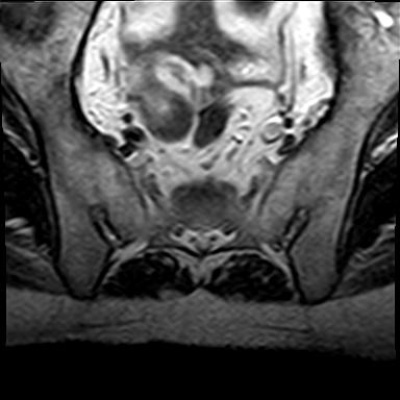

Chụp cộng hưởng từ (MRI) là kỹ thuật chẩn đoán hình ảnh không xâm lấn, cho phép tạo ra hình ảnh chi tiết các cấu trúc bên trong cơ thể, bao gồm các cơ quan, xương, cơ và mạch máu. Máy MRI là một thiết bị lớn, hình trụ, sử dụng từ trường mạnh và sóng radio để tạo ra hình ảnh, không sử dụng bức xạ ion hóa như chụp X-quang.

Từ trường này khiến các nguyên tử trong cơ thể sắp xếp theo cùng một hướng. Sau đó, máy phát ra các xung sóng radio, làm thay đổi hướng của các nguyên tử này. Khi sóng radio tắt, các nguyên tử trở về vị trí ban đầu và phát ra tín hiệu radio. Các tín hiệu này được máy vi tính xử lý để tạo ra hình ảnh chi tiết của bộ phận cơ thể cần khảo sát. Hình ảnh này được hiển thị trên màn hình để bác sĩ quan sát và phân tích.

Chụp MRI có thể được sử dụng để chẩn đoán các vấn đề về khớp, gồm:

Sau đây là một số hình ảnh viêm cột sống dính khớp trên X-quang: